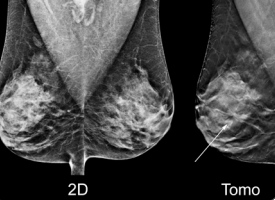

There will be eight 75-minute breast tomosynthesis education sessions from March 7-9. Each session includes hands-on experience reading breast tomosynthesis images in combination with conventional and generated (C-View) 2-D images.